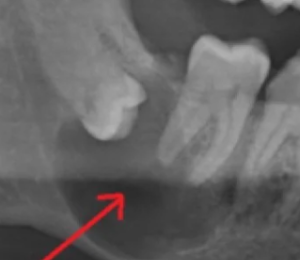

상기 사진처럼 사랑니가 턱뼈에 매복되어 있고 동그랗게 물혹을 만든 경우, 발치가 매우 필요합니다. 처음에는 물혹이 작다가 사이즈가 점점 커지면서 주변 치아에까지 퍼지고 턱뼈 안의 신경을 누르는 경우도 생기기 때문에 매복 사랑니는 되도록 발치를 하시는게 좋습니다.

만약 현재 통증도 없고 엑스레이상 문제가 없는 상태로, 발치가 부담스럽다면 주기적으로 정기 검진을 하셔야 합니다. 정기 검진 시 물혹이 생겼다거나 점점 커지는 것 같다고 하면 그때는 발치를 꼭 하셔야 합니다.